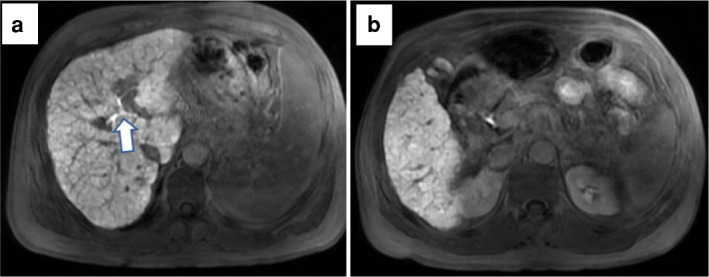

Materials and methods: Between April 2015 and December 2022, the HCC patients who underwent gadoxetic acid-enhanced MRI were analyzed. Three parameters on hepatobiliary phase images were evaluated for FLIS: liver parenchymal enhancement, biliary excretion, and signal intensity of the portal vein. The correlation between Child-Turcotte-Pugh (CTP) classification, the albumin-bilirubin (ALBI) grade, and Fibrosis-4 (F-4) score, and FLIS were analyzed. Receiver operating characteristic curve analysis was performed to demonstrate the cut-off value of FLIS for differentiating between CTP classification and ALBI grade.

Abstract Image